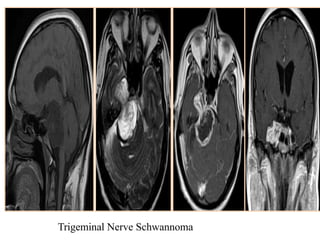

Schwannoma:

They are less commonly called neurinomas or neurilemmomas, are

benign tumours of Schwann cell origin and are the most common

tumour of peripheral nerves, including cranial nerves.

They may grow primarily in the parasellar region or extend posteriorly

through the porus trigeminus into the posterior fossa.

Tumor extension into the pterygoid fossa or paranasal sinuses occurs in

10% of cases.

The pressure exerted by the tumor leads to erosion of the underlying

bone and enlargement of the foramen ovale, foramen rotundum, or the

superior orbital fissure, which is better appreciated on thin-section

coronal-CT scans.

Trigeminal schwannomas typically follow the course of the fifth

cranial nerve and have a dumbbell-shaped configuration.

They are smoothly marginated tumors and are usually isointense

comparing to gray matter on T1WI and hyperintense on T2WI.

Small tumors are homogeneous; large tumors can have heterogeneous

signal intensity due to degenerative changes, including cyst formation

and fatty degeneration.

Trigeminal Nerve Schwannoma

Trigeminal schwannomas typicallyfollow the course of the fifth cranial nerve and have a dumbbell-shaped configuration. They are smoothly marginated tumors and are usually isointense comparing to gray matter on T1WI and hyperintense on T2WI. Small tumors are homogeneous; large tumors can have heterogeneous signal intensity due to degenerative changes, including cyst formation and fatty degeneration.

• #35 Schwannoma of the trigeminal nerve (T1-weighted sequences and T2).